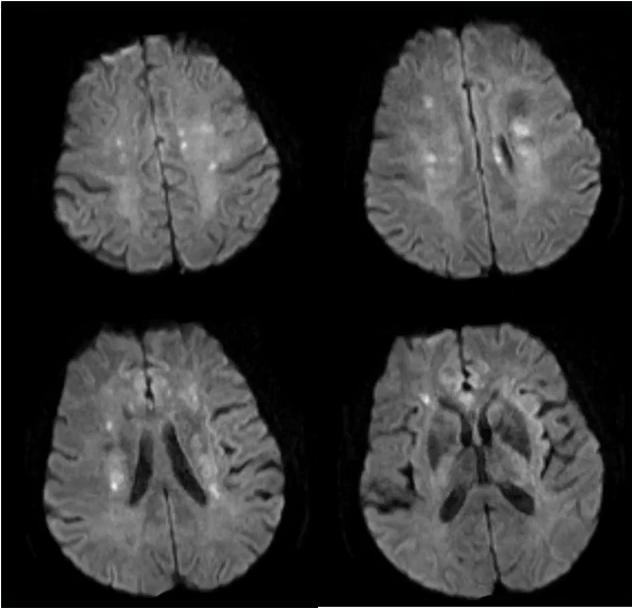

完善DWI示:双侧半球分水岭急性梗死。

除了DWI显示的双侧半球分水岭急性梗死,FLAIR发现多发脑白质高信号,累及双侧颞极。

1. 白质高信号,特征部位包括颞极、额极、外囊,如图蓝箭所指。

2. 腔隙,如图绿箭所指。

3. 微出血(MB),如图红箭所指。

4. 脑萎缩,如图白箭所指。